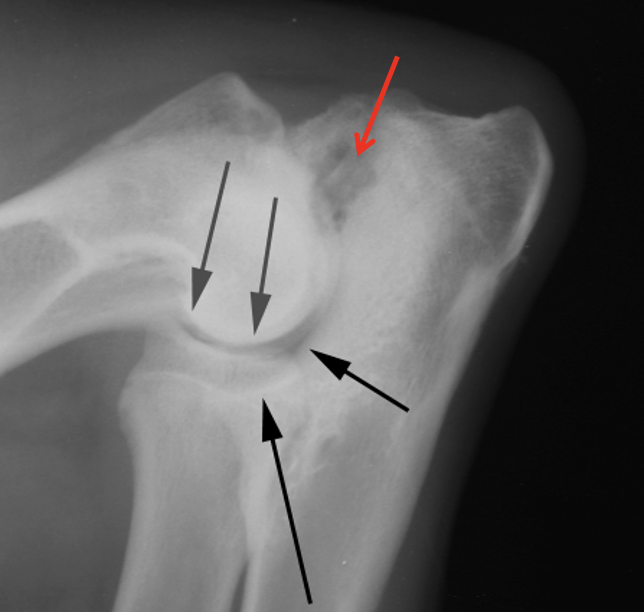

33

What is shown in this radiograph?

CCL rupture -intracapsular swelling -displacement of infrapatellar fat pat -displacement of fascial planes caudal to joint

34

avulsion fracture secondary to CCL rupture

35

DJD secondary to CCL rupture -osteophytes on patella, near trochlear groove, and on margins of tibial plateau and fabellae

36